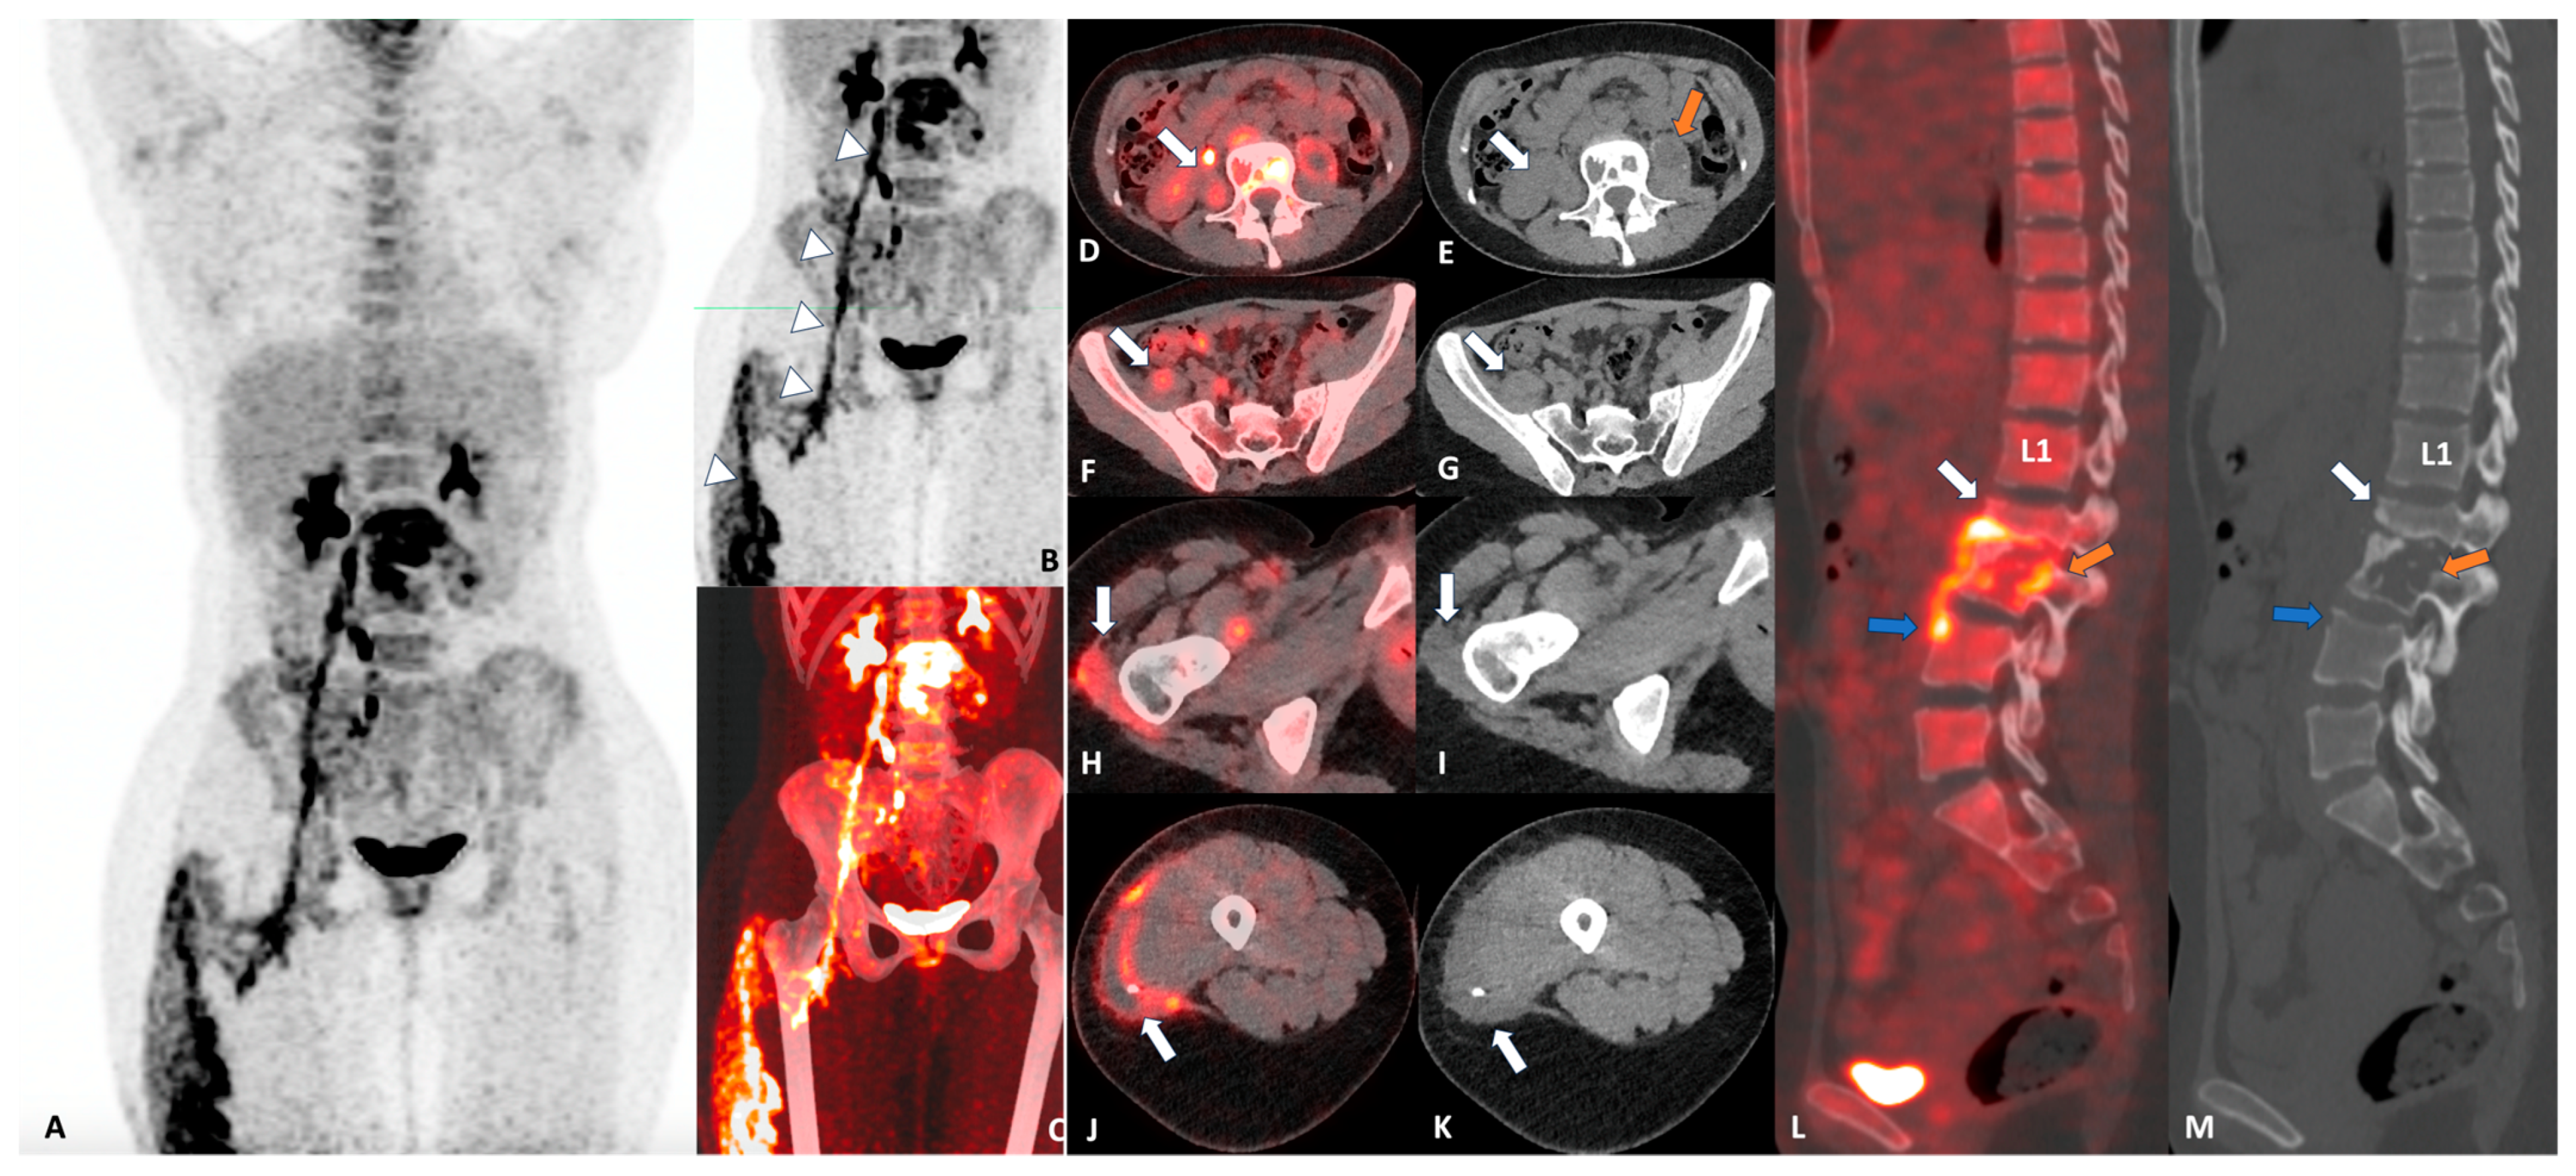

Tuberculous Spondylodiscitis with Psoas Abscess Descending into the Anterior Femoral Compartment Identified Using 2-deoxy-2-[18F]fluoroglucose Positron Emission Tomography Computed Tomography